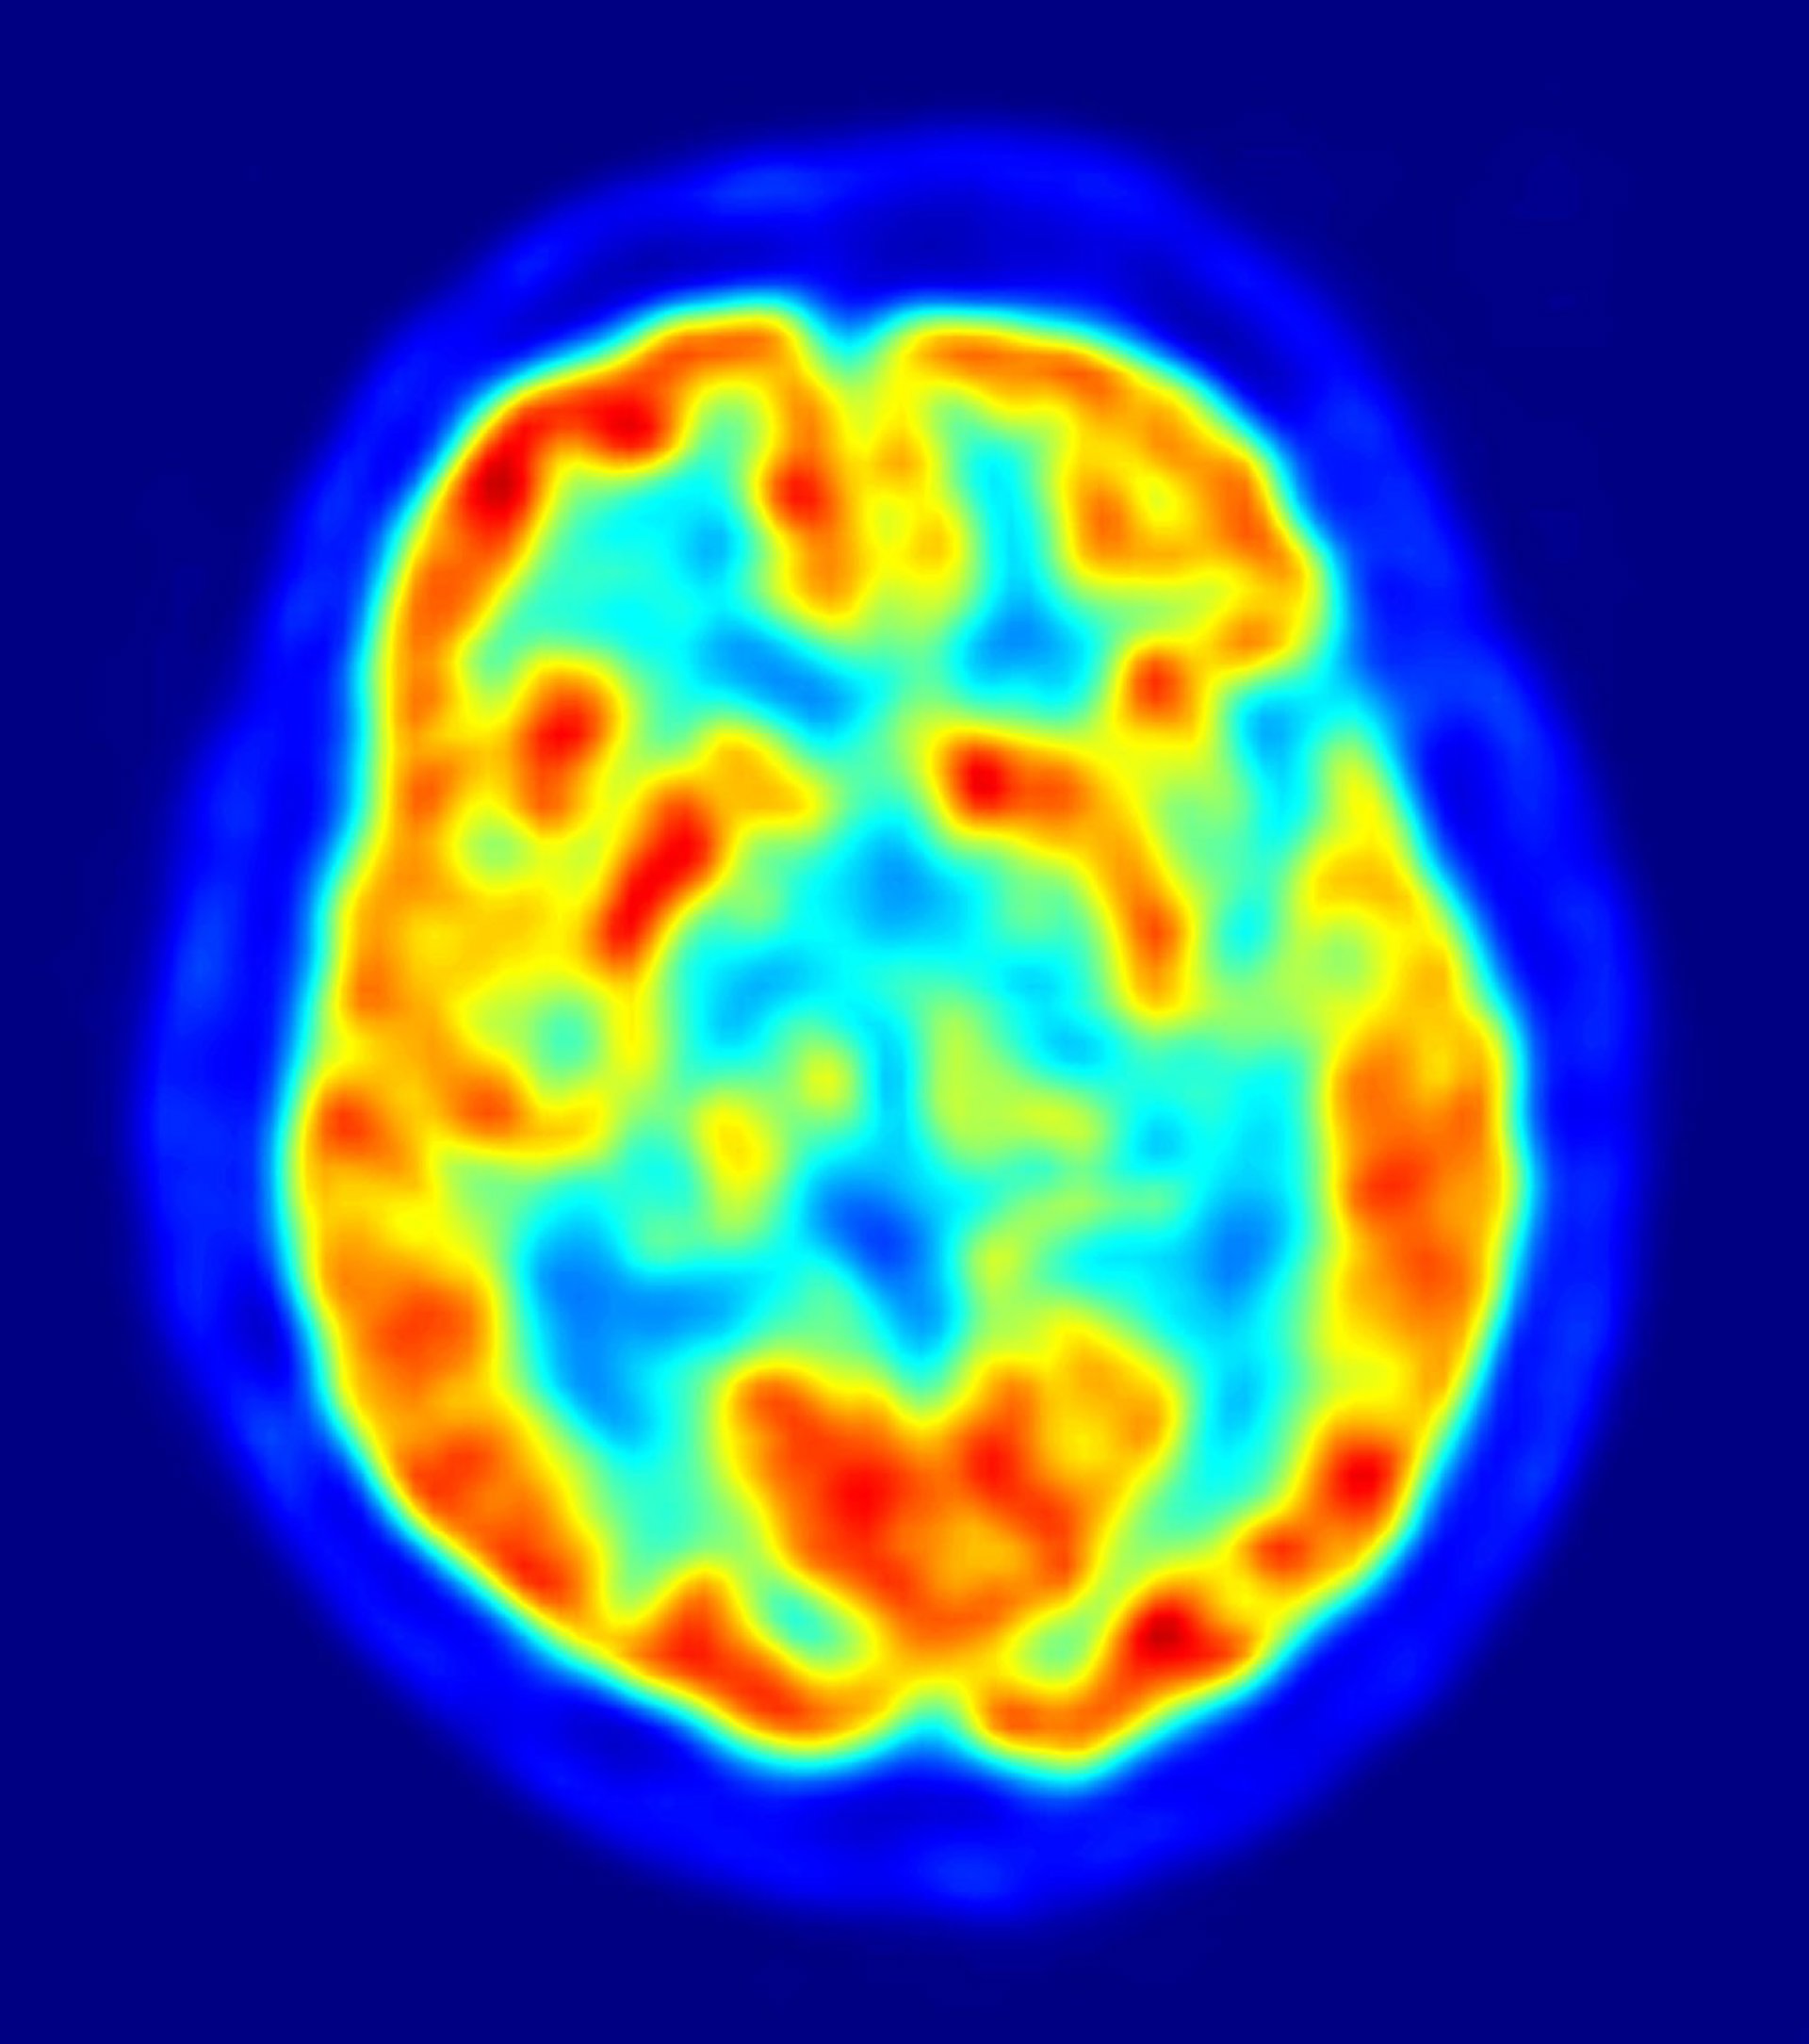

cerebro, recurso, neuronas

El ictus engloba un conjunto de enfermedades como la apoplejía, la embolia, trombosis y derrame cerebral, que se desencadenan con la oclusión o rotura de una arteria, lo que conlleva la muerte de células cerebrales y secuelas en forma de hemiplejia, afasia o parálisis.